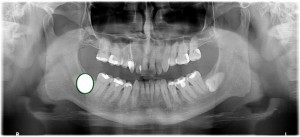

Wisdom teeth (there are 4) become very inflamed and painful when the patient is about 16 years and the jaw has insufficient space for the teeth to come through. Sometimes, these teeth try to force through in the wrong direction, called “impacted wisdom teeth”. This surgery needs great skill and experience and at Caring 4 Smiles, we perform this surgical procedure almost every day. To plan this difficult surgical procedure a Panoramic X-ray ($135) is the minimum for an accurate diagnosis, and sometimes in complex cases (like below), a 3D Cone Beam CT X-Ray ($300) is necessary.

Please see the attached Panoramic X-Rays of one of our patients. This was a very difficult surgery to extract the 2 lower wisdom teeth. Both sites needed large volumes of bone grafting. Had bone grafting not been done, the patient would have had significant post-operative complications due to the unfilled dead space which may or may not have filled over time.